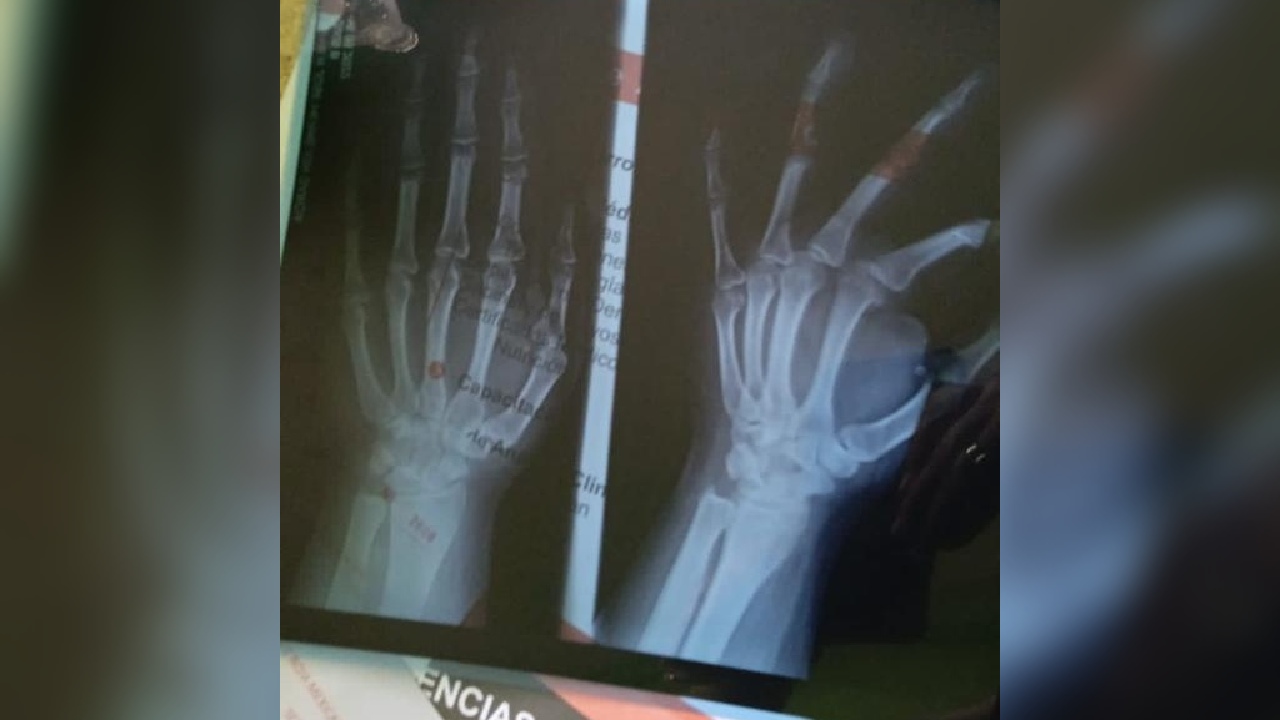

Las agresiones contra Mario*, el joven de 15 años, han venido subiendo de tono, detalló en entrevista. Debido a que la madre del joven es lesbiana, consideró que la violencia radica en la lesbofobia que los adolescentes manifiestan en su agresión. Y esta ha escalado niveles, pues a Mario* le fracturaron la mano derecha y le provocaron diversas lesiones que fueron atendidas en el servicio médico de la Cruz Roja durante la madrugada del lunes 16 de mayo de 2022.